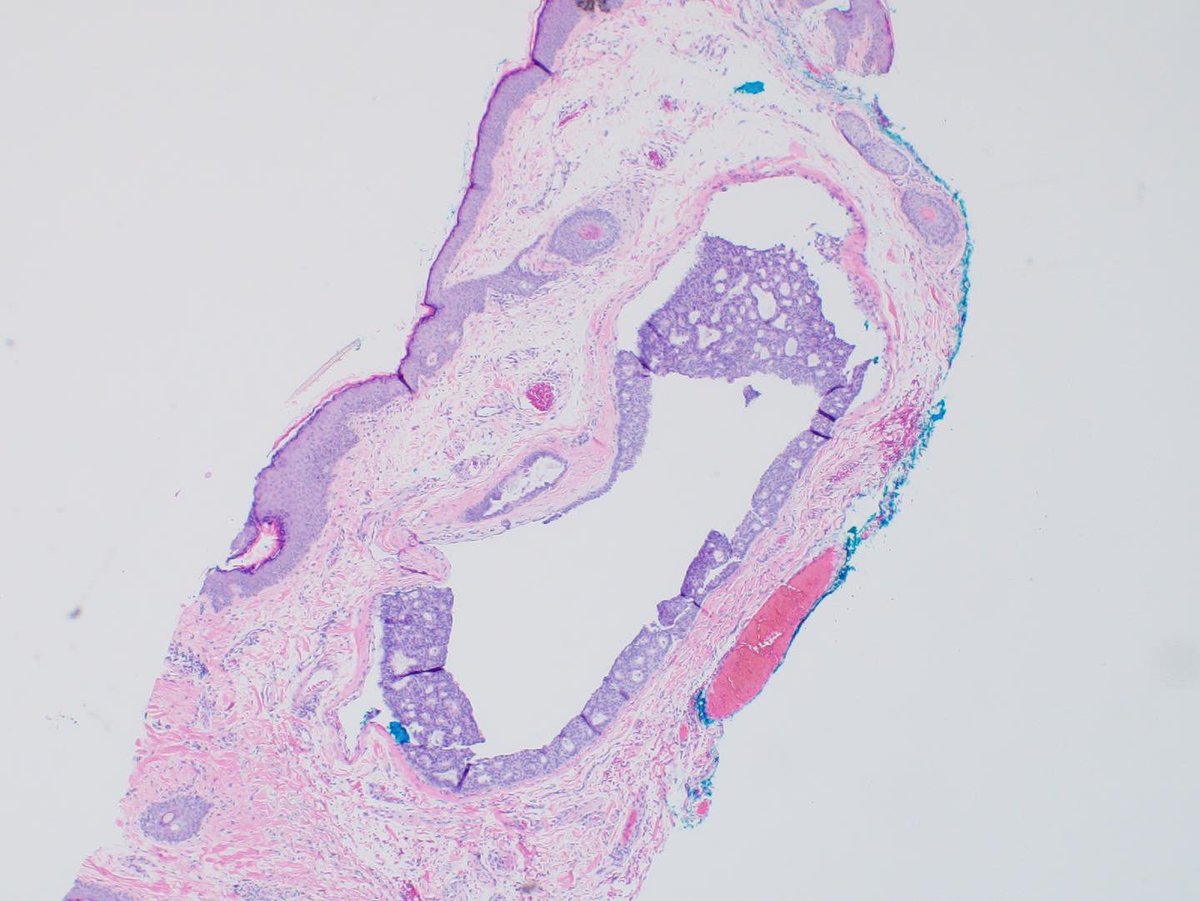

Endocrine mucin-producing sweat gland carcinoma of eyelid. What needs to be ruled out here? 1. Ink on paper 2-3. H&E 4. PR #neuropath #neuropathology #eyepathology #ophthalmology #inktober #inktober2022